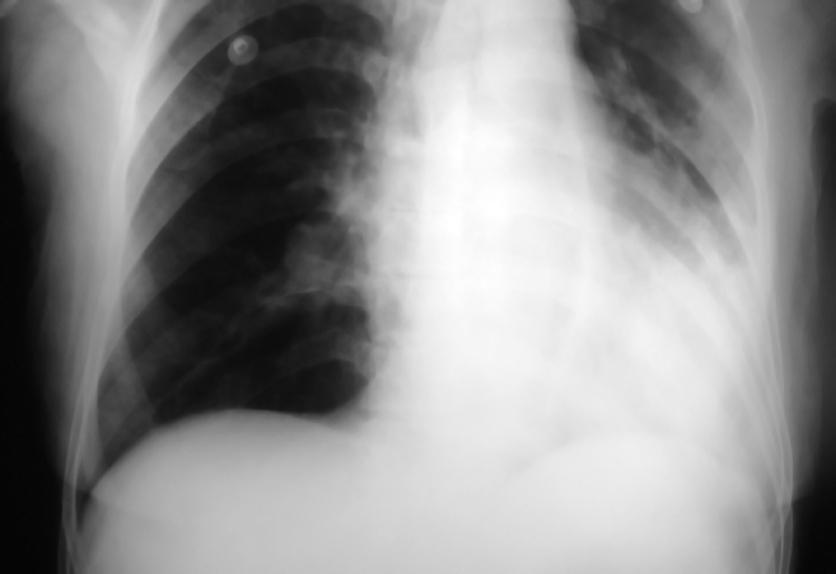

Discussion Question Resource: Chest X-Ray